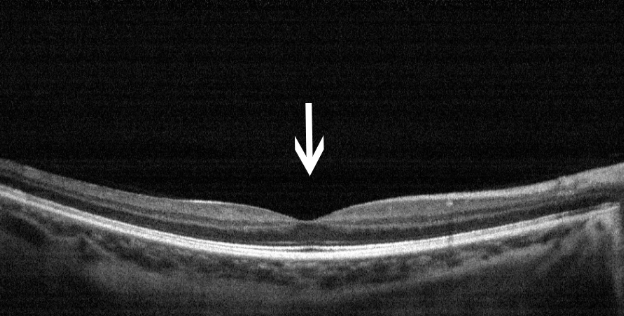

这是一个正常的后极部眼底彩照及黄斑区OCT图。

OCT:黄斑区视网膜的断面图,凹陷处为黄斑中心凹